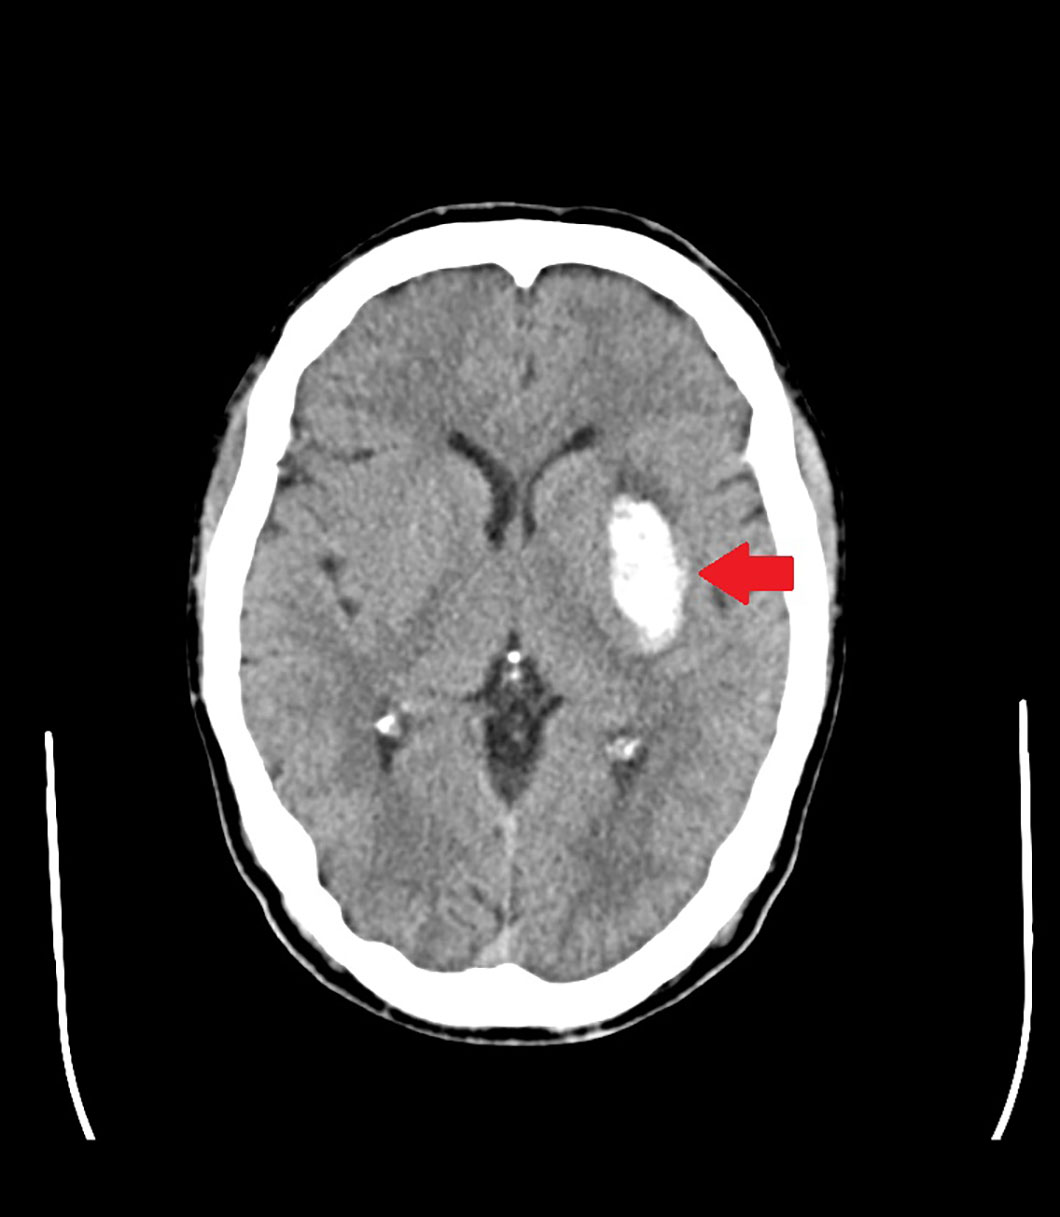

脳出血

症状

頭痛や麻痺